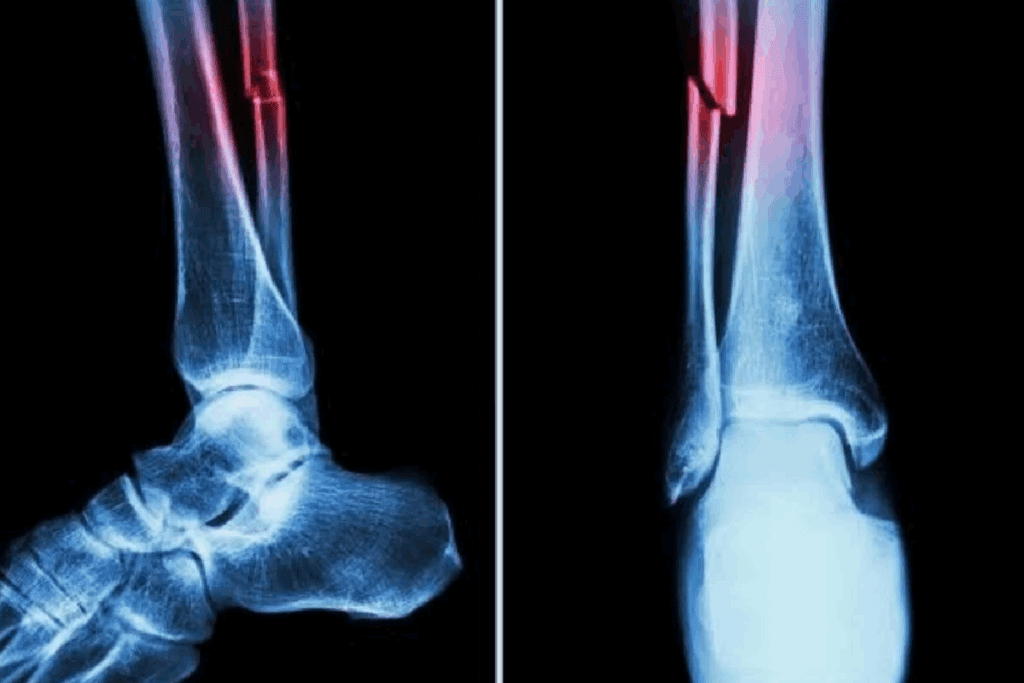

Imaging Techniques: X-rays, CT Scans, and MRIs

Imaging is key to confirming bone fractures. The right imaging depends on the fracture type, location, and patient’s health.

Common imaging techniques used include:

- X-rays: The first-line imaging modality for most suspected fractures, providing a quick and effective way to visualize bone structures.

- CT scans: Useful for complex fractures or when more detailed imaging is required, specially in cases involving multiple fragments or overlapping bones.

- MRIs: Particular value for detecting soft tissue injuries and stress fractures that may not be visible on X-rays.

Detecting Subtle Fractures and Hairline Cracks

Stress fractures or hairline cracks can be hard to spot. They might not show up on first X-rays. Advanced imaging like MRI or CT scans are used to confirm these injuries.